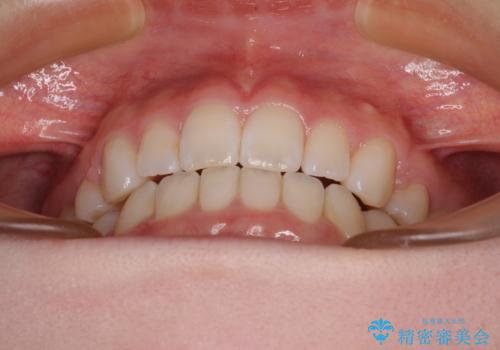

- 前歯の出っ歯と口元の閉じにくさを気にして来院された患者様です。

口元を積極的に引っ込めるために、上下左右の小臼歯4本を抜歯することとしました。

4本の歯を抜歯したことで、飛び出していた口元が引っ込み、横顔が大きく改善されました。